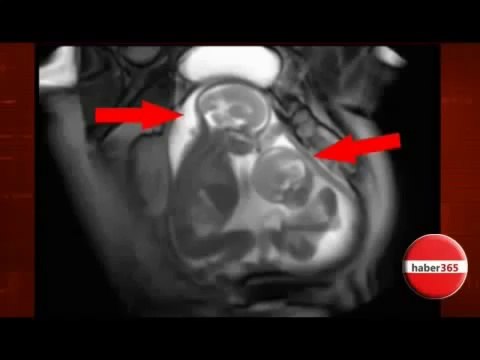

kendini, anne, karnında, zanneden, ikiz, bebekler, twin, babies, womb, thought, himself